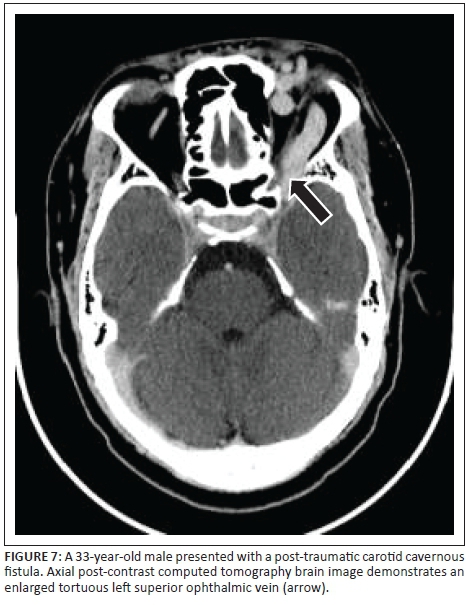

A dilated superior ophthalmic vein is often the initial finding on imaging and was found in 96% of the reviewed image data in our study, which compared favourably to other reports of 86% - 100% on enhanced CT and 75% - 100% on T1W or post-contrast MRI.4 Other findings on axial imaging include proptosis, retrobulbar fat stranding, sinus distension and early/avid enhancement of the affected CS (see Figures 7 and 9). In addition, CT allows easier identification of fractures and complications such as haemorrhage, whereas MRI allows the detection of abnormal flow voids within the CS. Magnetic resonance is understood to be superior to CT in detection of subtle signs.4